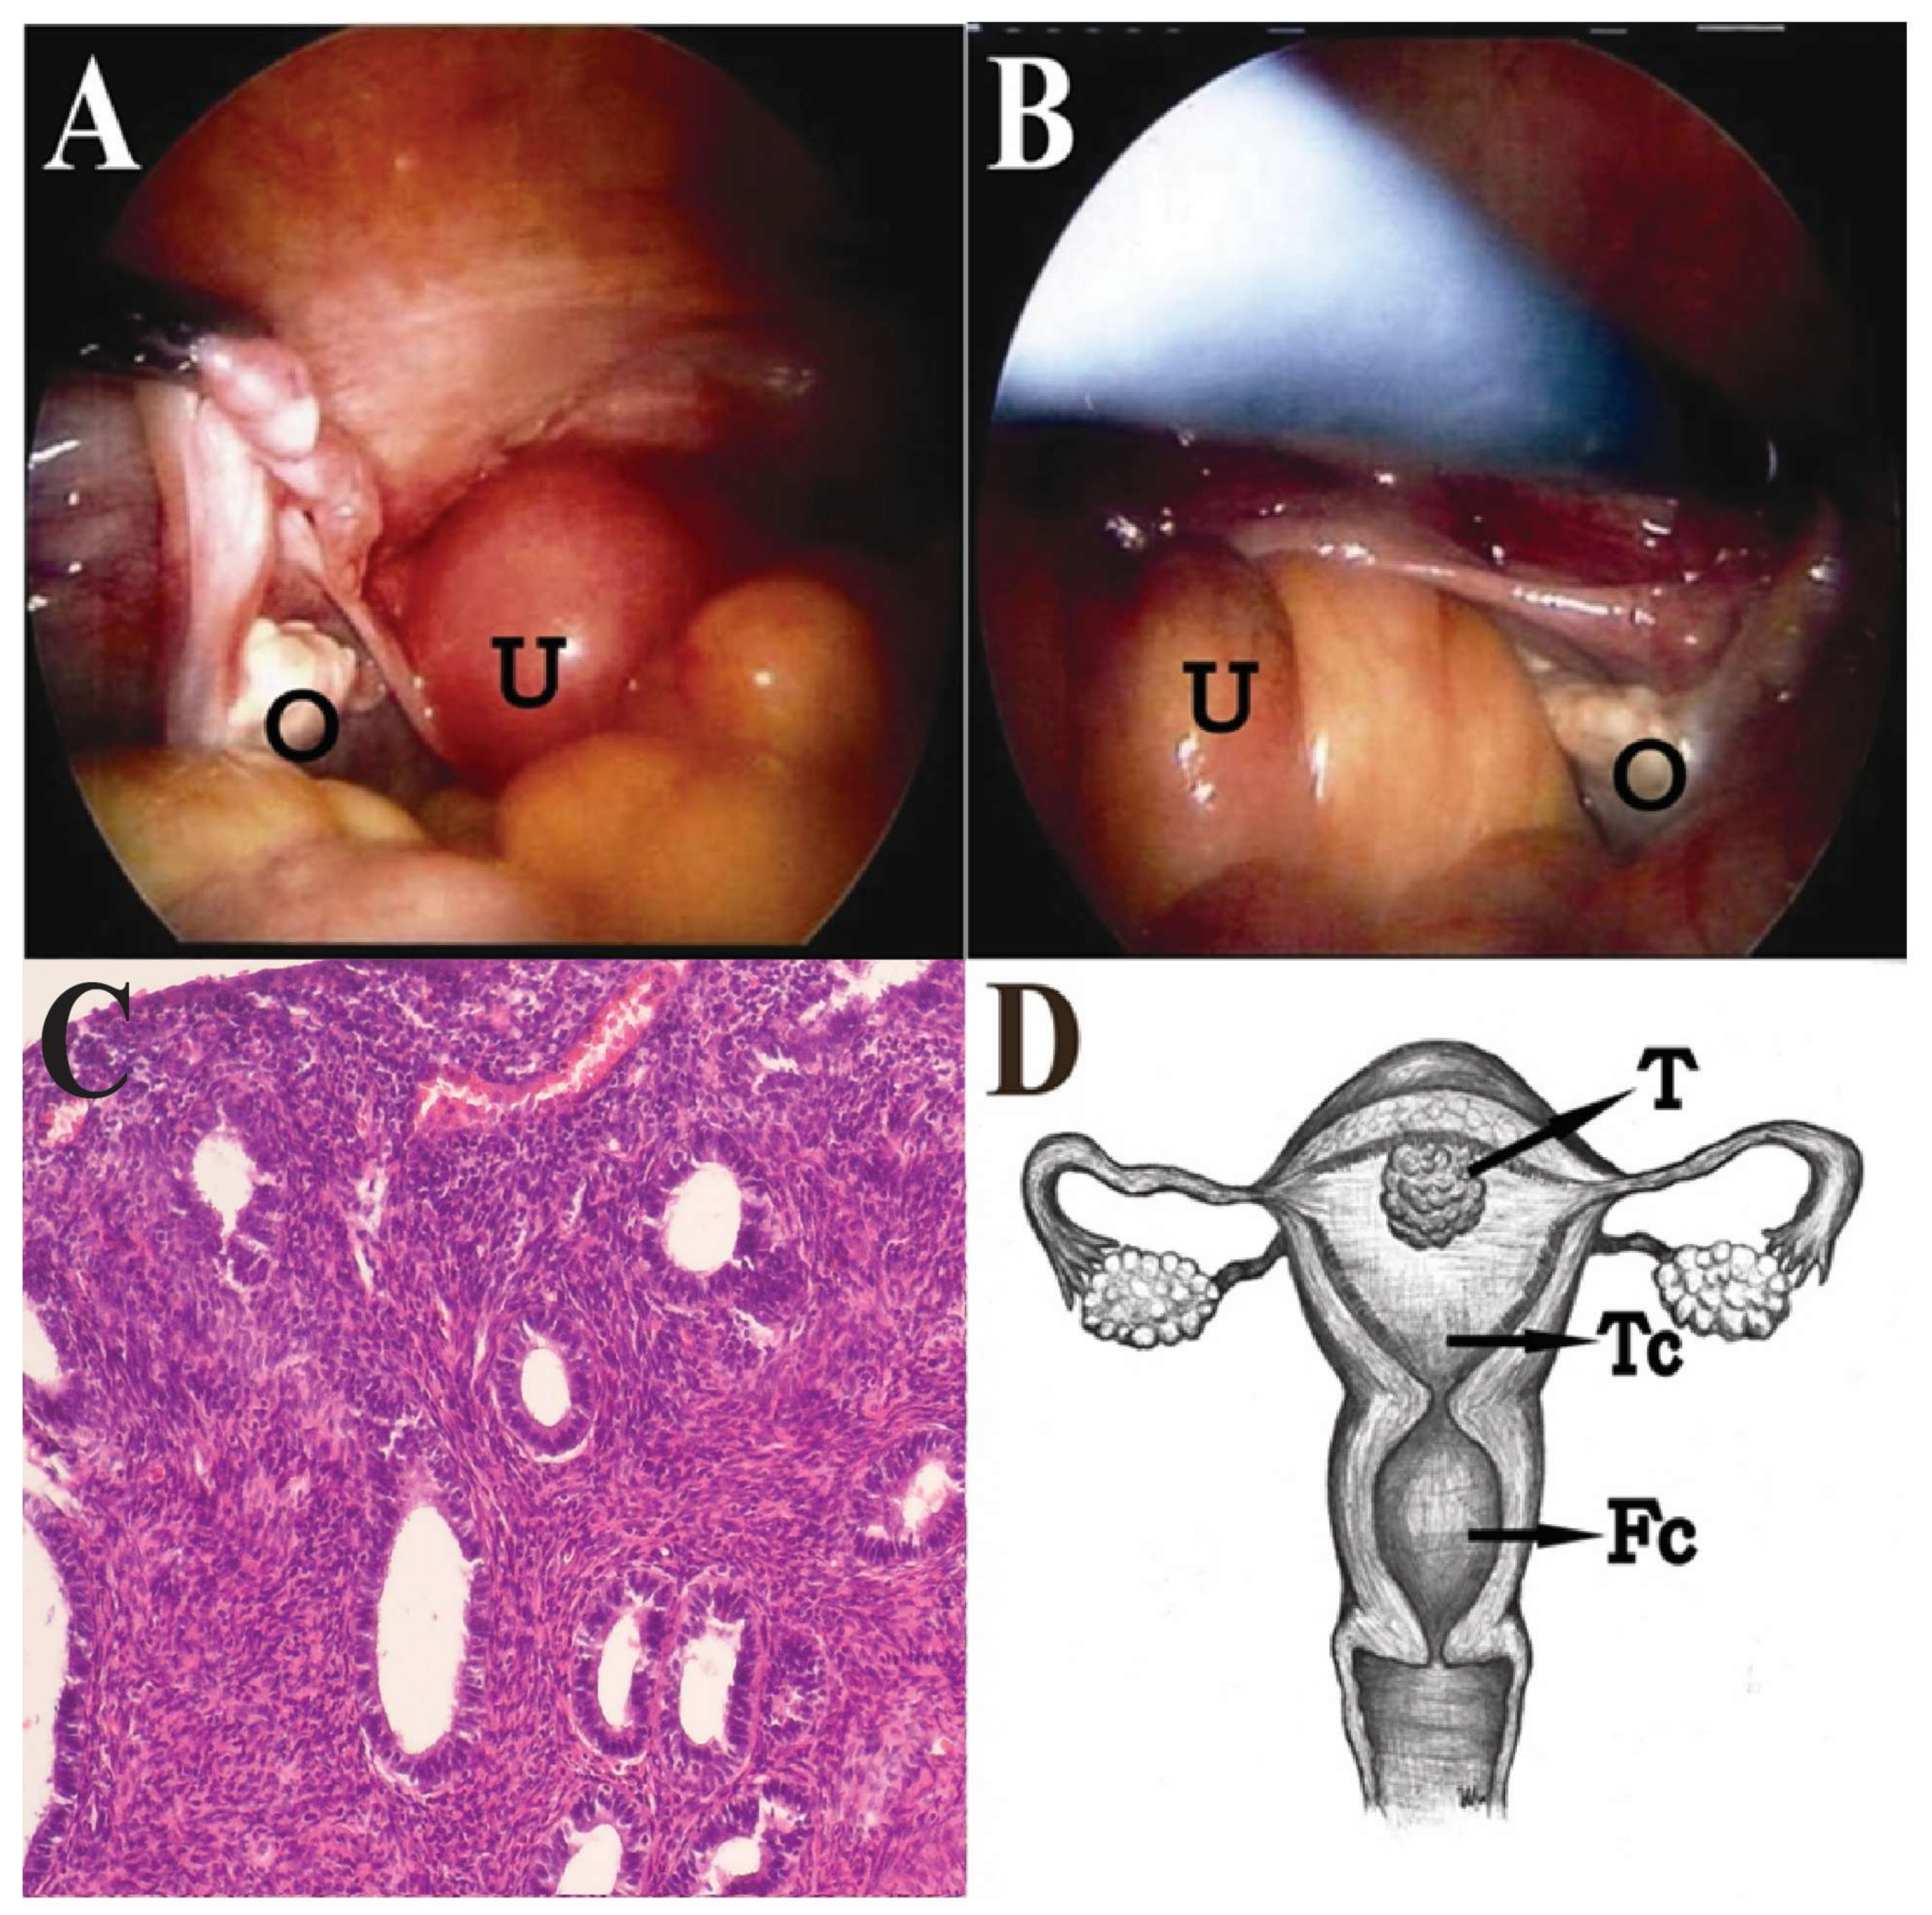

Hysteroscopy and D&C were performed again, but only revealed a small and atrophic “uterine cavity”. The pathological report of the D&C was normal endometrial glands and chronic cervicitis. Under the impression of adnexal tumor with suspicion of fallopian tube or ovarian cancer, she received a diagnostic laparoscopy. During surgery, atrophic uterus, ovaries and fallopian tubes were noted, but no adnexal tumor was found (

Figure 3A,B). Laparoscopic-assisted vaginal hysterectomy and bilateral salpingo-oophorectomy were done. When the uterus was opened, two cavities were noted: the true uterine cavity was filled with old blood and necrotic tumors, and the lower cavity was actually a dilated endocervical cavity. A 1.5-cm pseudo-polypoid tumor was found on the superficial endometrium in the true uterine cavity. Finally, a pathology report revealed endometrioid adenocarcinoma of endometrium, stage 1a, grade 3, with squamous differentiation (

Figure 3C,D). After surgery, the symptoms were relieved, and the patient refused to receive complete staging surgery. The other adjuvant treatments, such as radiation therapy and brachytherapy, were suggested to this intermediate-risk patient due to grade 3 with squamous differentiation. However, the patient decided to observation after surgical intervention. During two years follow up, there was no evidence of local recurrence, and the patient received regular follow up at outpatient department. A written informed consent was obtained from the patient.